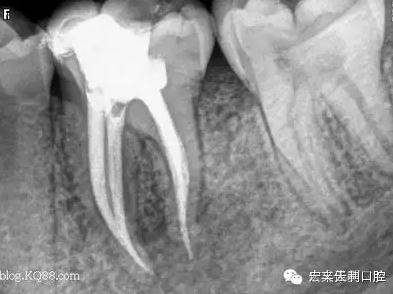

例如,我們有位女患者,在我們門診部根管治療結(jié)束后,建議她做個(gè)牙冠保護(hù)起來,她當(dāng)時(shí)沒有聽取意見,過了三個(gè)月左右牙已劈裂。沒有任何辦法補(bǔ)救了,只能選擇拔掉一半,之前做的根管治療也前功盡棄。如圖:

1.jpg

2.jpg